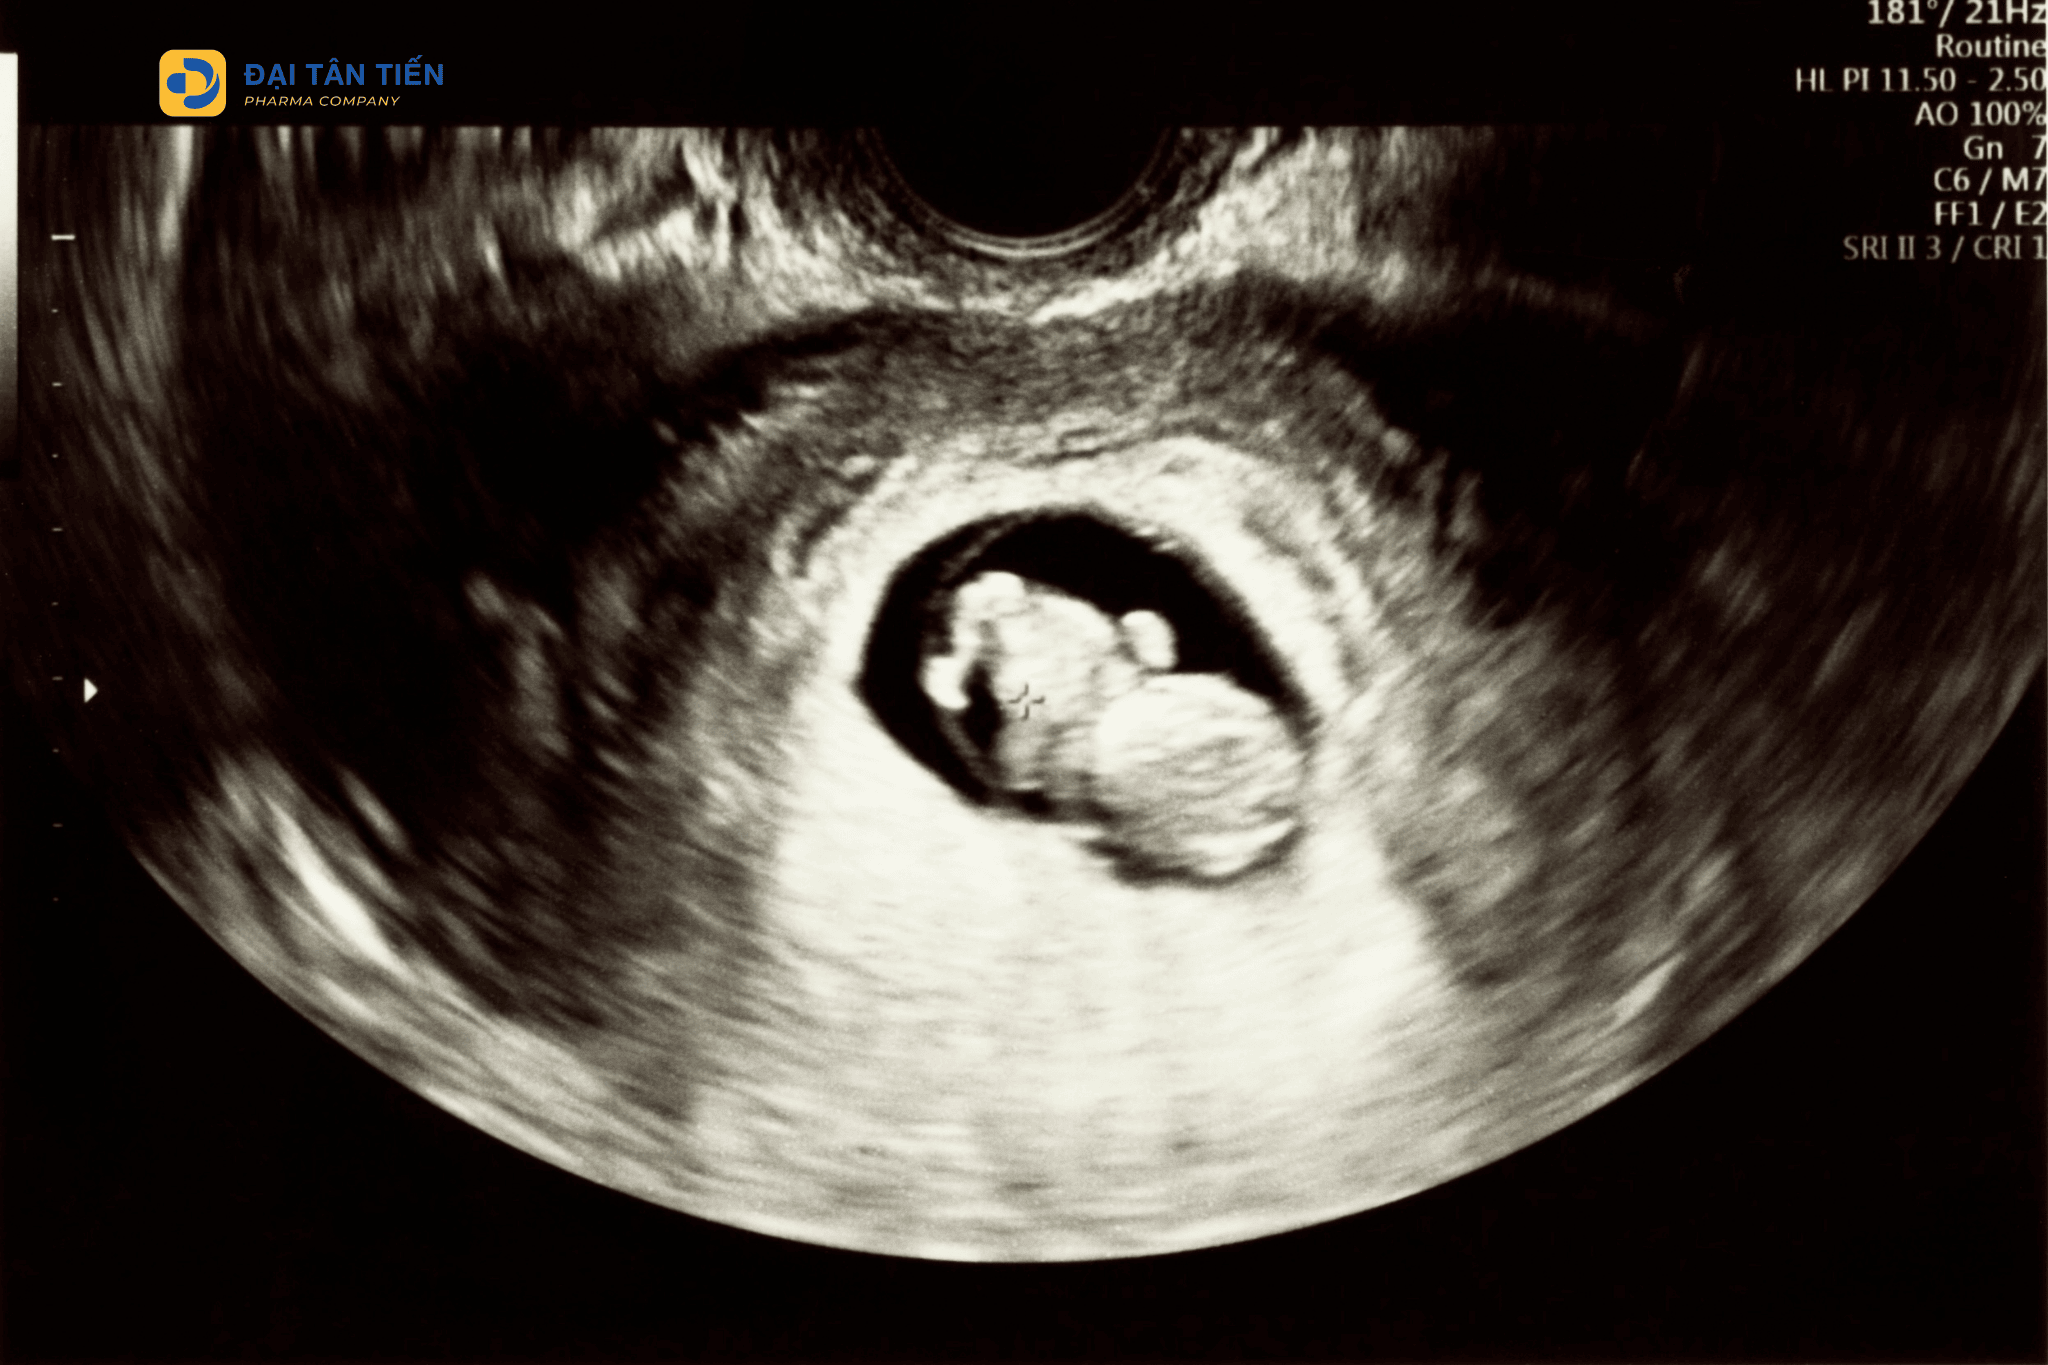

Siêu âm là phương pháp giúp xác nhận thai kỳ và theo dõi sự phát triển của phôi thai trong giai đoạn đầu.

Mặc dù các dấu hiệu mang thai sớm có thể giúp nhận biết thai kỳ, nhưng chúng không đủ để xác định chắc chắn.

Để xác nhận mang thai, phụ nữ có thể:

• sử dụng que thử thai

• xét nghiệm máu đo hormone hCG

• thăm khám tại cơ sở y tế